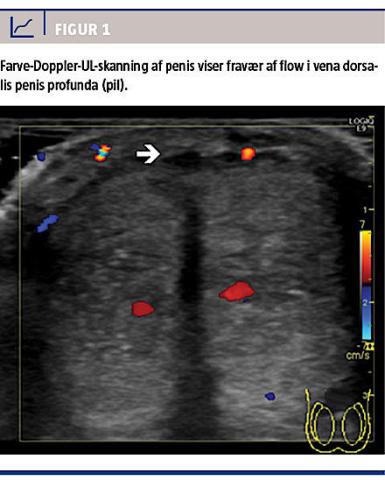

Rødme og hævelse tiltog over de næste timer og medinddrog hele glans og corpus penis strækkende sig ud på mons pubis og scrotum. Penis var spontant erigeret, og der var hævelse med pitting ødem og let hydrocele. En kant af glans penis var blåcyanotisk. Ved et tilsyn af en organkirurgisk bagvagt blev Fourniers gangræn udelukket. Rødme og hævelse tiltog yderligere i løbet af aftenen, og patienten blev sent på aftenen overflyttet til et universitetshospital. En farve-Doppler-UL-skanning af penis viste trombose i det proksimale stykke af VDPP samt ophørt flow distalt i samme vene (Figur 1).